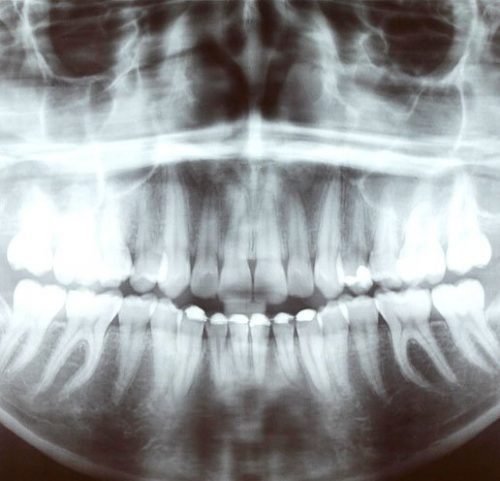

Las clínicas dentales han tenido en las últimas décadas a las radiografías dentales como grandes ayudantes a la hora de detectar e identificar los problemas y percances en las estructuras dentales de sus pacientes.

No obstante, la modernización de esta técnica ha incrementado su eficiencia y usabilidad. En los últimos años han surgido dos nuevos métodos, como la radiovisiografía dental digital, que se están desarrollando y que presentan múltiples ventajas respeto a las radiografías convencionales.

Uno de los puntos a favor de la radiovisiografía dental digital es la menor dosis de radiación a la que se expone el paciente a la hora de llevar a cabo la prueba. Este es un punto importante, ya que la radiación siempre es perjudicial para la salud. En segundo lugar, al no ser necesario usar películas radiográficas y su respectivo proceso químico de revelado, imlpica una mejora económica respeto a las radiografías convencionales y una reducción del coste.

Otra ventaja es que la radiovisiografía dental presenta una menor distorsión de la imagen, por lo que los resultados son más claros y el diagnóstico del dentista es más completo, detallado y preciso. Asimismo, la imagen es más precisa en relación a la profundidad de las lesiones y por lo tanto se pone otra piedra para construir un tratamiento exitoso y satisfactorio para el paciente. Por último, la digitalización radiográfica permite una mayor posibilidad de almacenamiento y transmisión de los resultados.